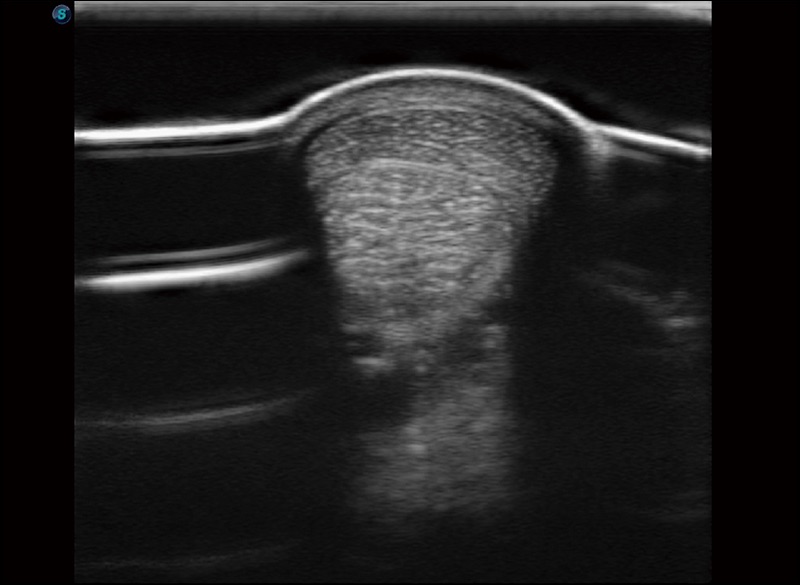

α1卓越的图像质量和便捷的工作流程,使每位宠物医生都能轻松扫查。其全面的兽用应用功能和紧凑型的结构设计,可以满足动物检查的多种需要。专业的预设检查模式和多领域测量软件包有助于为不同类型的动物提供检查, 让宠物医生能够出色的完成工作。

支持线阵和凸阵探头,一键操作即可获得更宽的图像视野

实时宽景成像

可实时观察感兴趣区域和病变位置